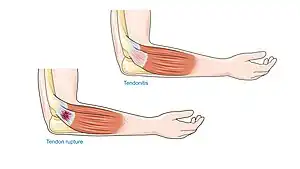

Diagram illustrating tendonitis and tendon rupture

Symptoms can vary from aches or pains and local joint stiffness, to a burning that surrounds the whole joint around the inflamed tendon. In some cases, swelling occurs along with heat and redness, and there may be visible knots surrounding the joint. With this condition, the pain is usually worse during and after activity, and the tendon and joint area can become stiff the following day as muscles tighten from the movement of the tendon. Many patients report stressful situations in their life in correlation with the beginnings of pain which may contribute to the symptoms.